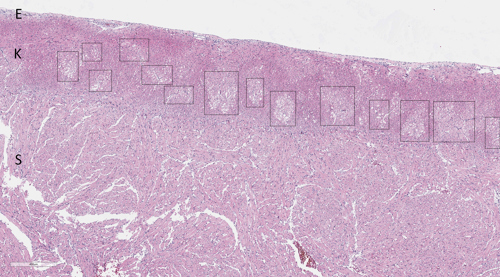

Bilde: Bildet viser vevssnitt fra hjerte fra laks. Det sees lysere områder med myokarddegenerasjon rundt forgreninger av koronararterier. E = epikard, K = kompakt hjertemuskulatur, S = spongiøs hjertemuskulatur, kk = forgreninger av koronararterier.